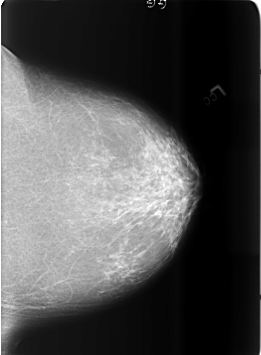

B_3465_1.RIGHT_CC

LEFT_CC LINES 5680 PIXELS_PER_LINE 4176 BITS_PER_PIXEL 12 RESOLUTION 50 NON_OVERLAY